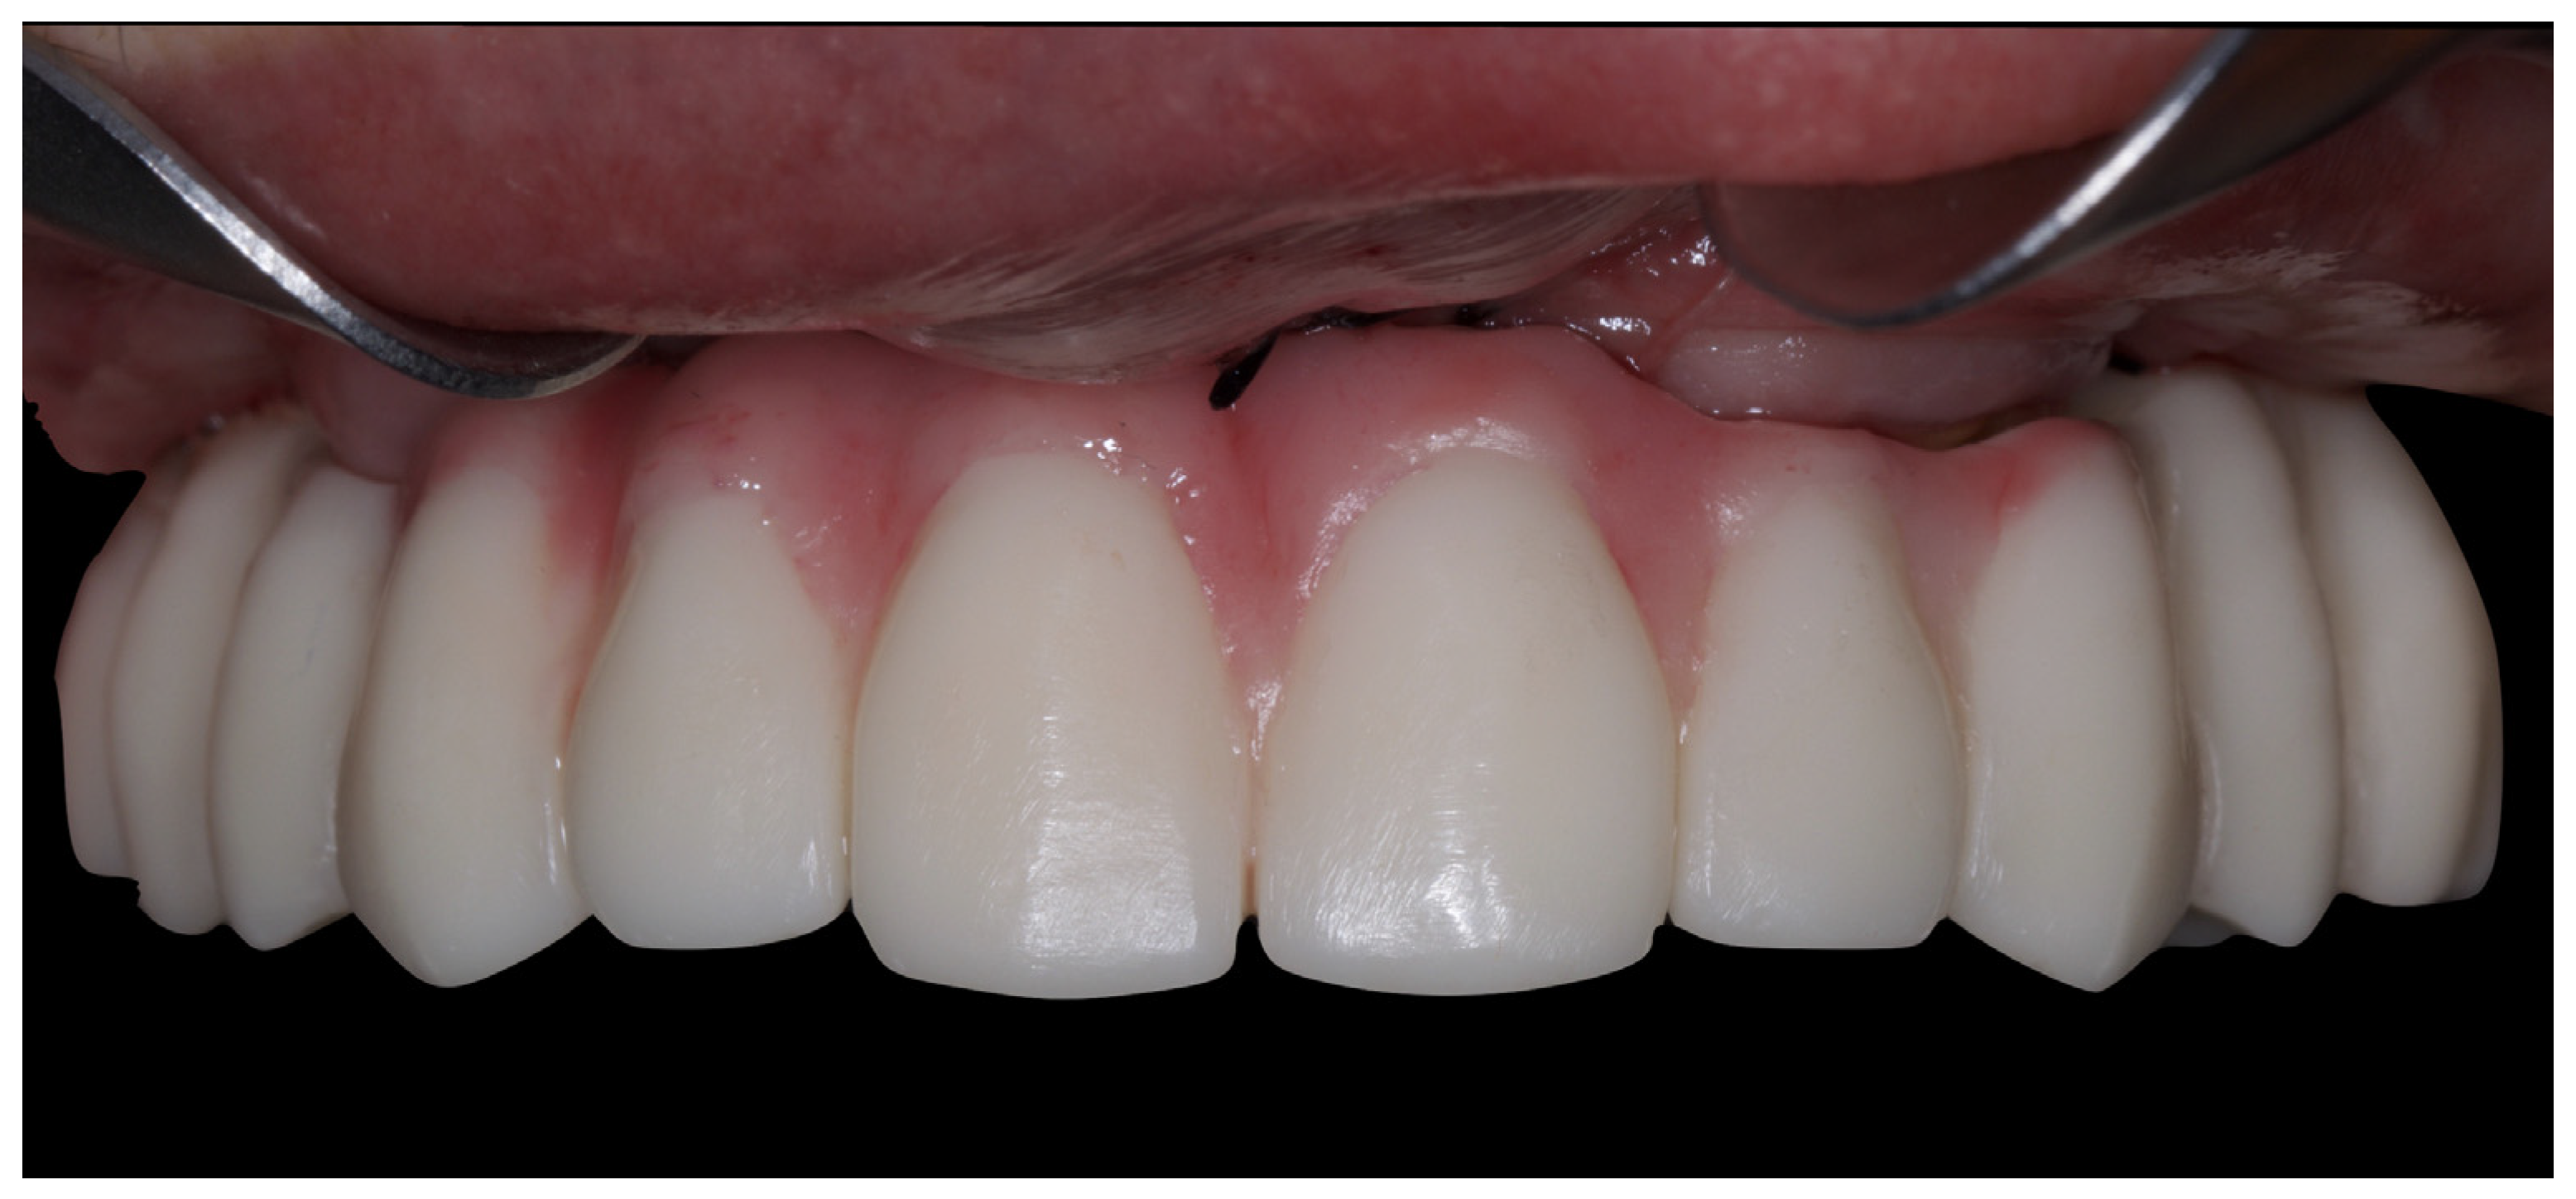

3. Results